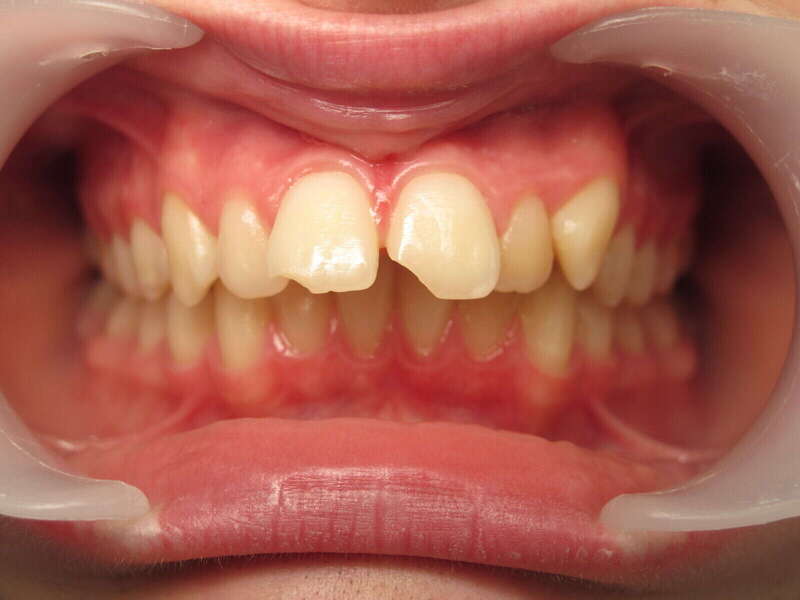

Cas n°1 traité par aligneurs - adolescent

Ce cas d’une adolescente illustre la correction d'une Classe II avec supraclusion par aligneurs. La stratégie thérapeutique a reposé sur une distalisation séquentielle de l'arcade supérieure. Ce mouvement précis a permis de reculer les dents maxillaires étape par étape pour annuler le surplomb (overjet) sans extractions.

• Correction fonctionnelle : Retour à un engrènement de Classe I stable et correction du recouvrement vertical.

• Esthétique restaurée : Harmonisation globale du sourire et du profil.

• Approche moderne : Un traitement discret, confortable et hautement prévisible.

Le résultat final montre une occlusion saine et un sourire parfaitement aligné, garantissant une santé dentaire et articulaire optimale pour l'avenir.